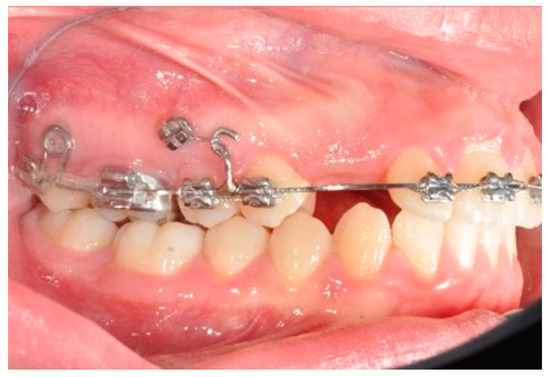

Once the upper first molars reach the hyper-first-class position, the tads are repositioned exactly mesial to the first molar. The solder distal to the bicuspid is removed and a new one is made distal to the ideal cuspid position. A power chain from the first molar (blocked with a metallic ligature with the second molar) to the second bicuspid and a coil spring between the solder and the first bicuspid allow for the simultaneous distalization of the second and first bicuspids (Figure 7).

Figure 7. Molar and premolar distalization strategy: Power chain from the first molar (blocked with a metallic ligature with the second molar) to the second bicuspid and coil spring between the solder and the first bicuspid allow for the simultaneous distalization of the second and first bicuspids.